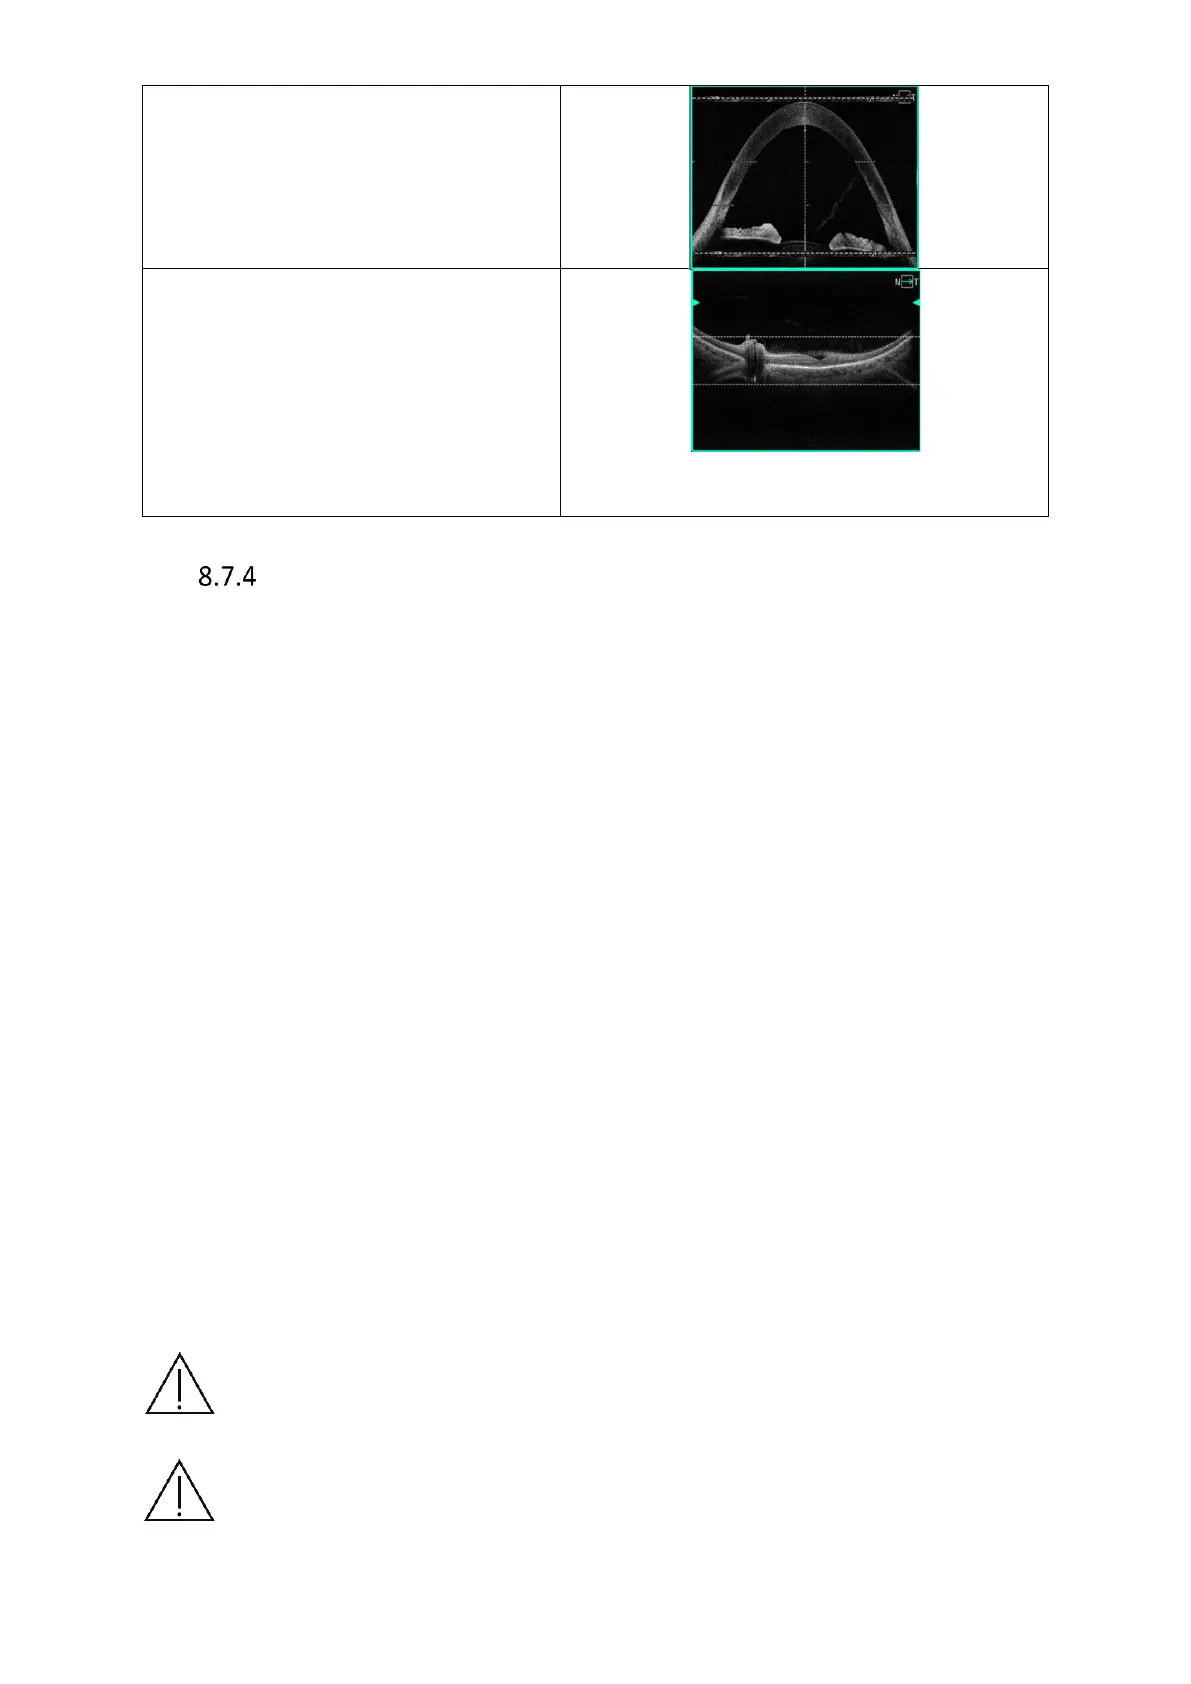

Full Range Anterior, make sure the

cornea is aligned with the dashed vertical

line, align the cornea between the

dashed horizontal lines.

Full Range Posterior, for the best image

quality align the retina between the two

dashed horizontal lines indicating the

area with the highest scanning

sensitivity. If, however, the user wants to

broaden the visualization range above or

below the retina, the image can be

aligned below or above the dashed lines.